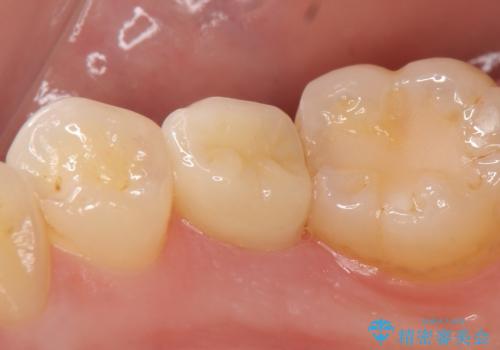

右下5は虫歯が大きく神経は保存不可能だったため、根管治療を行った後、オールセラミッククラウンによる補綴を行いました。

今回用いたオールセラミッククラウンはジルコニアフレームという白い素材の上にセラミックを盛っているため、審美性が非常に高いのが特徴です。

また、ジルコニアは人工ダイヤモンドの材料にも使われているほど高い強度を持っており、そのためオールセラミッククラウンは審美性だけでなく、奥歯やブリッジの補綴も可能とするクラウンです。